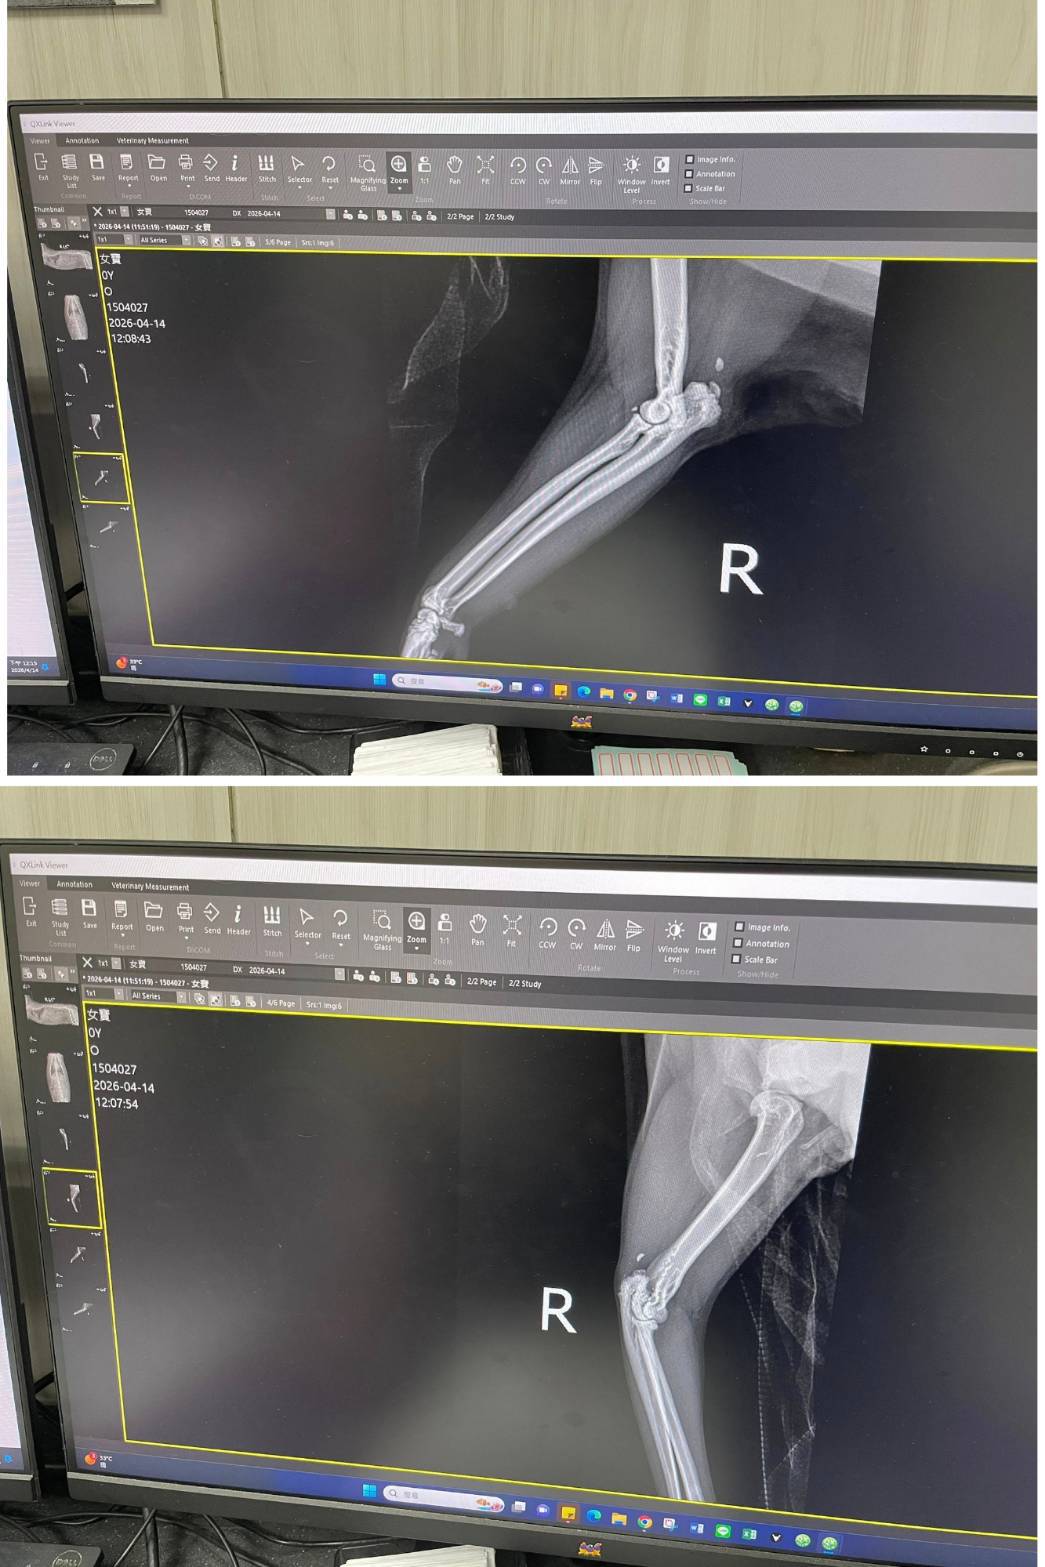

經X光檢查發現右前肢骨骼退化較嚴重,左邊也有一點骨骼退化;肺功能也是偏差;有牙周炎、牙齦萎縮所以齒根比較出來。X光有拍到兩顆東西,穿刺抹片檢查,淋巴細胞正常,淋巴結腫大。於醫院先點一錠除,並開立內用驅蟲藥,三個月後體外驅蟲需要再做一次。目前已於14日當日就醫後先行安置於協會幾日,因考量女寶年齡已大,汐止愛媽會帶回家中安置給女寶一個長久安穩的家。本筆醫助是女寶2026年4月14日於沐恩醫院看診的費用,包含血檢、X光、三合一、心臟快篩、皮膚抹片、一錠除滴劑及驅蟲藥。

右前肢比較嚴重左邊也有一點骨骼退化。

X光有拍到兩顆東西,穿刺抹片檢查,淋巴細胞正常,淋巴結腫大,